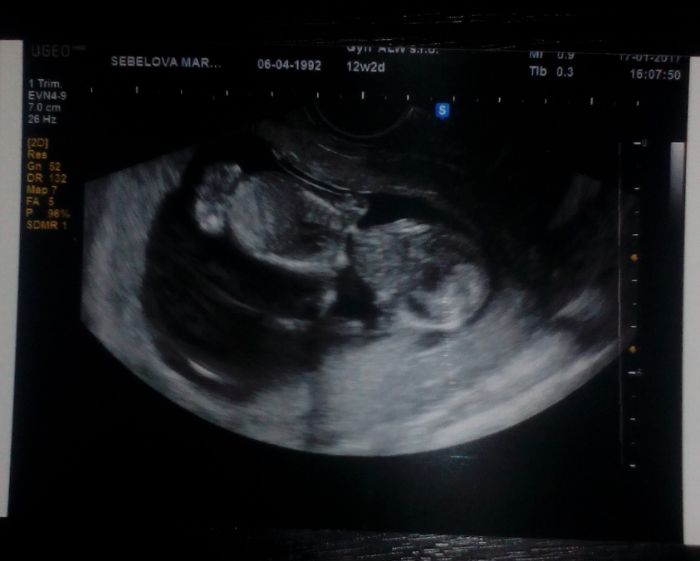

Ahojte, doufám že vám nevadí že se k vám chci přidat :-) , Dnes jsem byla v poradně jsem 12+2 tt . Termín porodu 30.7. :-)